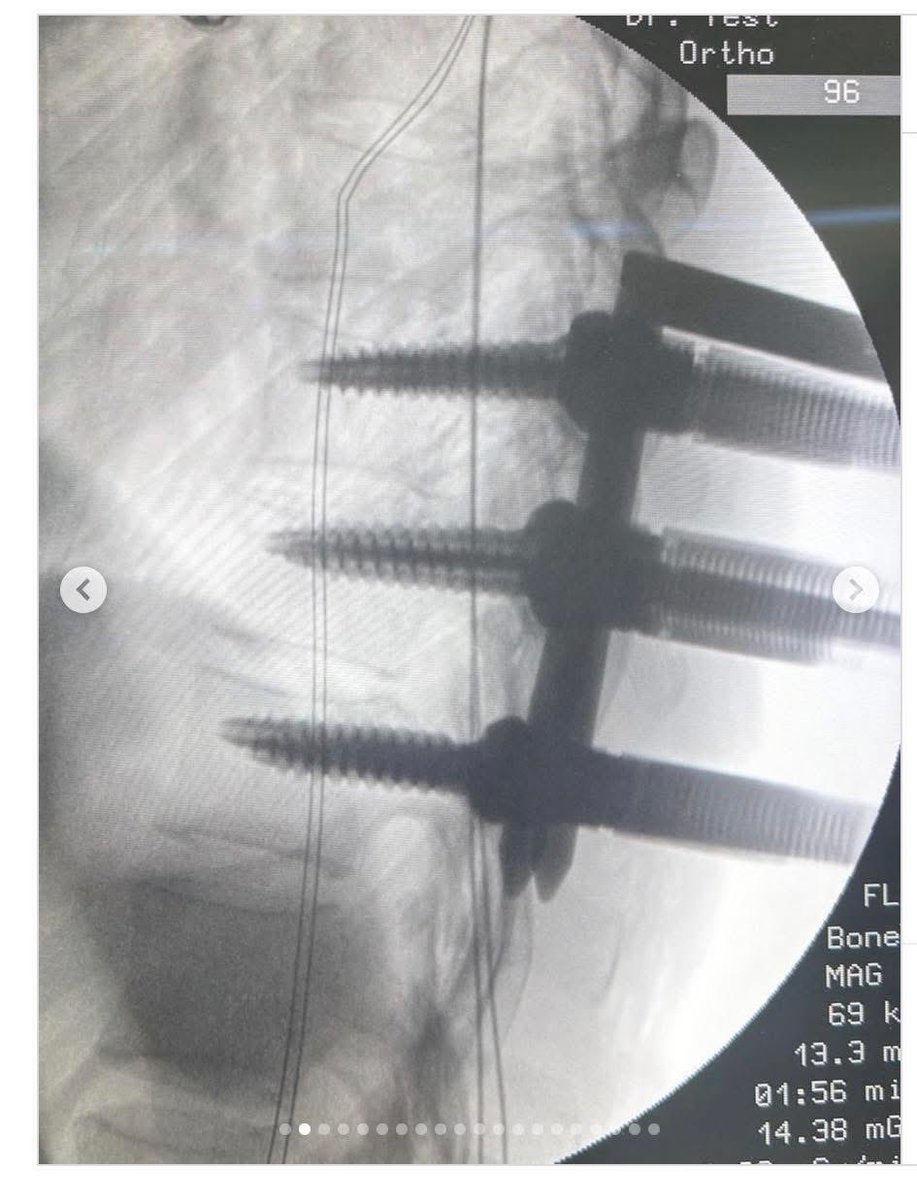

คุณหมอนั่ง grab ไปทำงาน จู่ๆขับฝ่าไฟแดง โดนชน ประสบอุบัติเหตุสาหัส ได้รับบาดเจ็บที่ศีรษะ กระดูกสันหลังหัก แต่โคตรโชคดีเลยที่ไขสันหลังไม่เป็นอะไร วอนผู้ให้บริการแอปเหล่านี้ ช่วยกวดขันเรื่องความปลอดภัยของคนขับด้วย